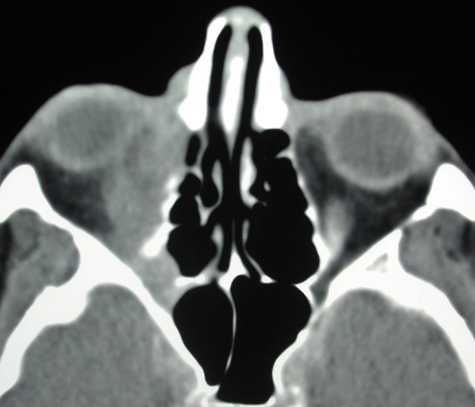

CT is particularly useful for imaging orbital and subperiosteal abscesses. Because the periorbit is not adherent to the orbital walls except at the suture lines, an abscess lifts the periorbit, creating a convexity in the orbital periosteum (Fig. 16). Usually subperiosteal abscess formation occurs adjacent to the involved sinus,25,64 but occasionally it occurs at a remote location such as the superolateral orbit.65 Gas may be found within a subperiosteal abscess or within the orbit, arising either from gas-forming bacilli or free communication with sinus air or from prior trauma (Fig. 17). 57,66 CT cannot accurately predict whether a subperiosteal mass represents exudate, inflammatory transudate, or hematoma.67,68

Fig. 17. Intraorbital gas in a 58-year-old patient with orbital cellulitis from a left frontal sinus mucocele. Gas appears as an area of complete radiolucency on this computed tomographic image.

A subperiosteal abscess may rupture or invade the periorbit, resulting in an orbital abscess. This may or may not be contiguous with the subperiosteal collection on CT. There may be gas or air–fluid levels within the mass.51,56,58,59 An orbital abscess may present as an enhancing ringlike peripheral mass that can be either heterogeneous or homogeneous (Fig. 18).

Fig. 18. Orbital abscess. A. Computed tomography of an orbital abscess presenting as an enhancing intraconal mass on right side. B. T1-weighted image. C. T2-weighted image. Note area of high signal corresponding to abscess.